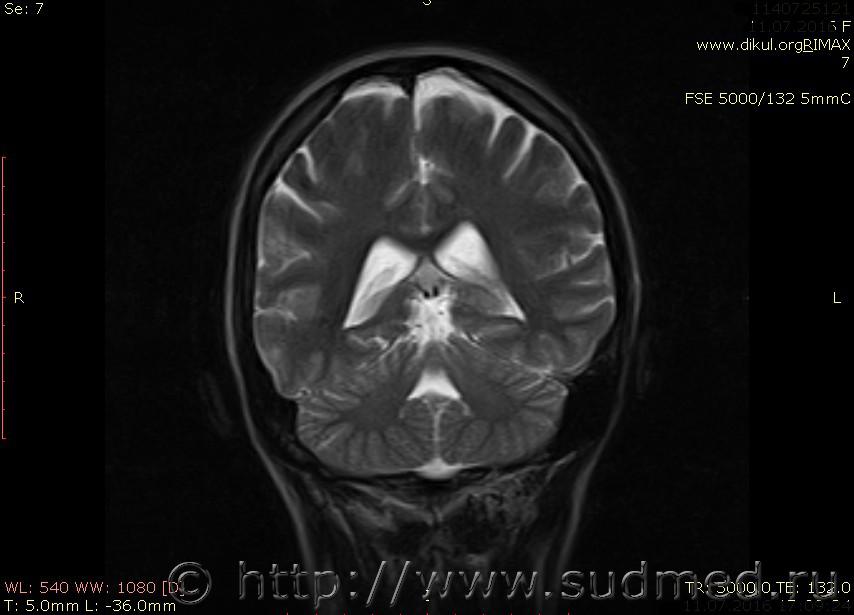

МРТ головного мозга показало: МР-данных за наличие очаговых изменений в веществе головного мозга на момент исследования не выявлено. МР-признаки нарушения соотношения в атланто-осевом суставе. Определяется ассиметрия положения зубовидного отростка С2 относительно боковых масс С1(справа 6,5; слева 4 мм.)

Сама по себе эта информация даёт основания подозревать вывих первого шейного позвонка, но однозначно не свидетельствует о наличии вывиха. Нужно смотреть на снимках наличие реакции со стороны мягких тканей, в т.ч. связочного аппарата, нужно анализировать особенности неврологической патологии, её динамику и проч.

Запрошен электронный вариант снимков из учреждения, где делалось МРТ. Т.к. с самого снимка делать копии не получается,очень мелкие кадры. Завтра попробую вставить в сообщение. (Но СМЭ снимок не смотрел, смотрел только мед.карту, в которой находилось описание МРТ).

Посмотрите пожалуйста снимки, надеюсь на них видны позвонки С1,С2?

Прошу прощения, попробую снова прикрепить файлы. Данные учреждения и пациента убраны.